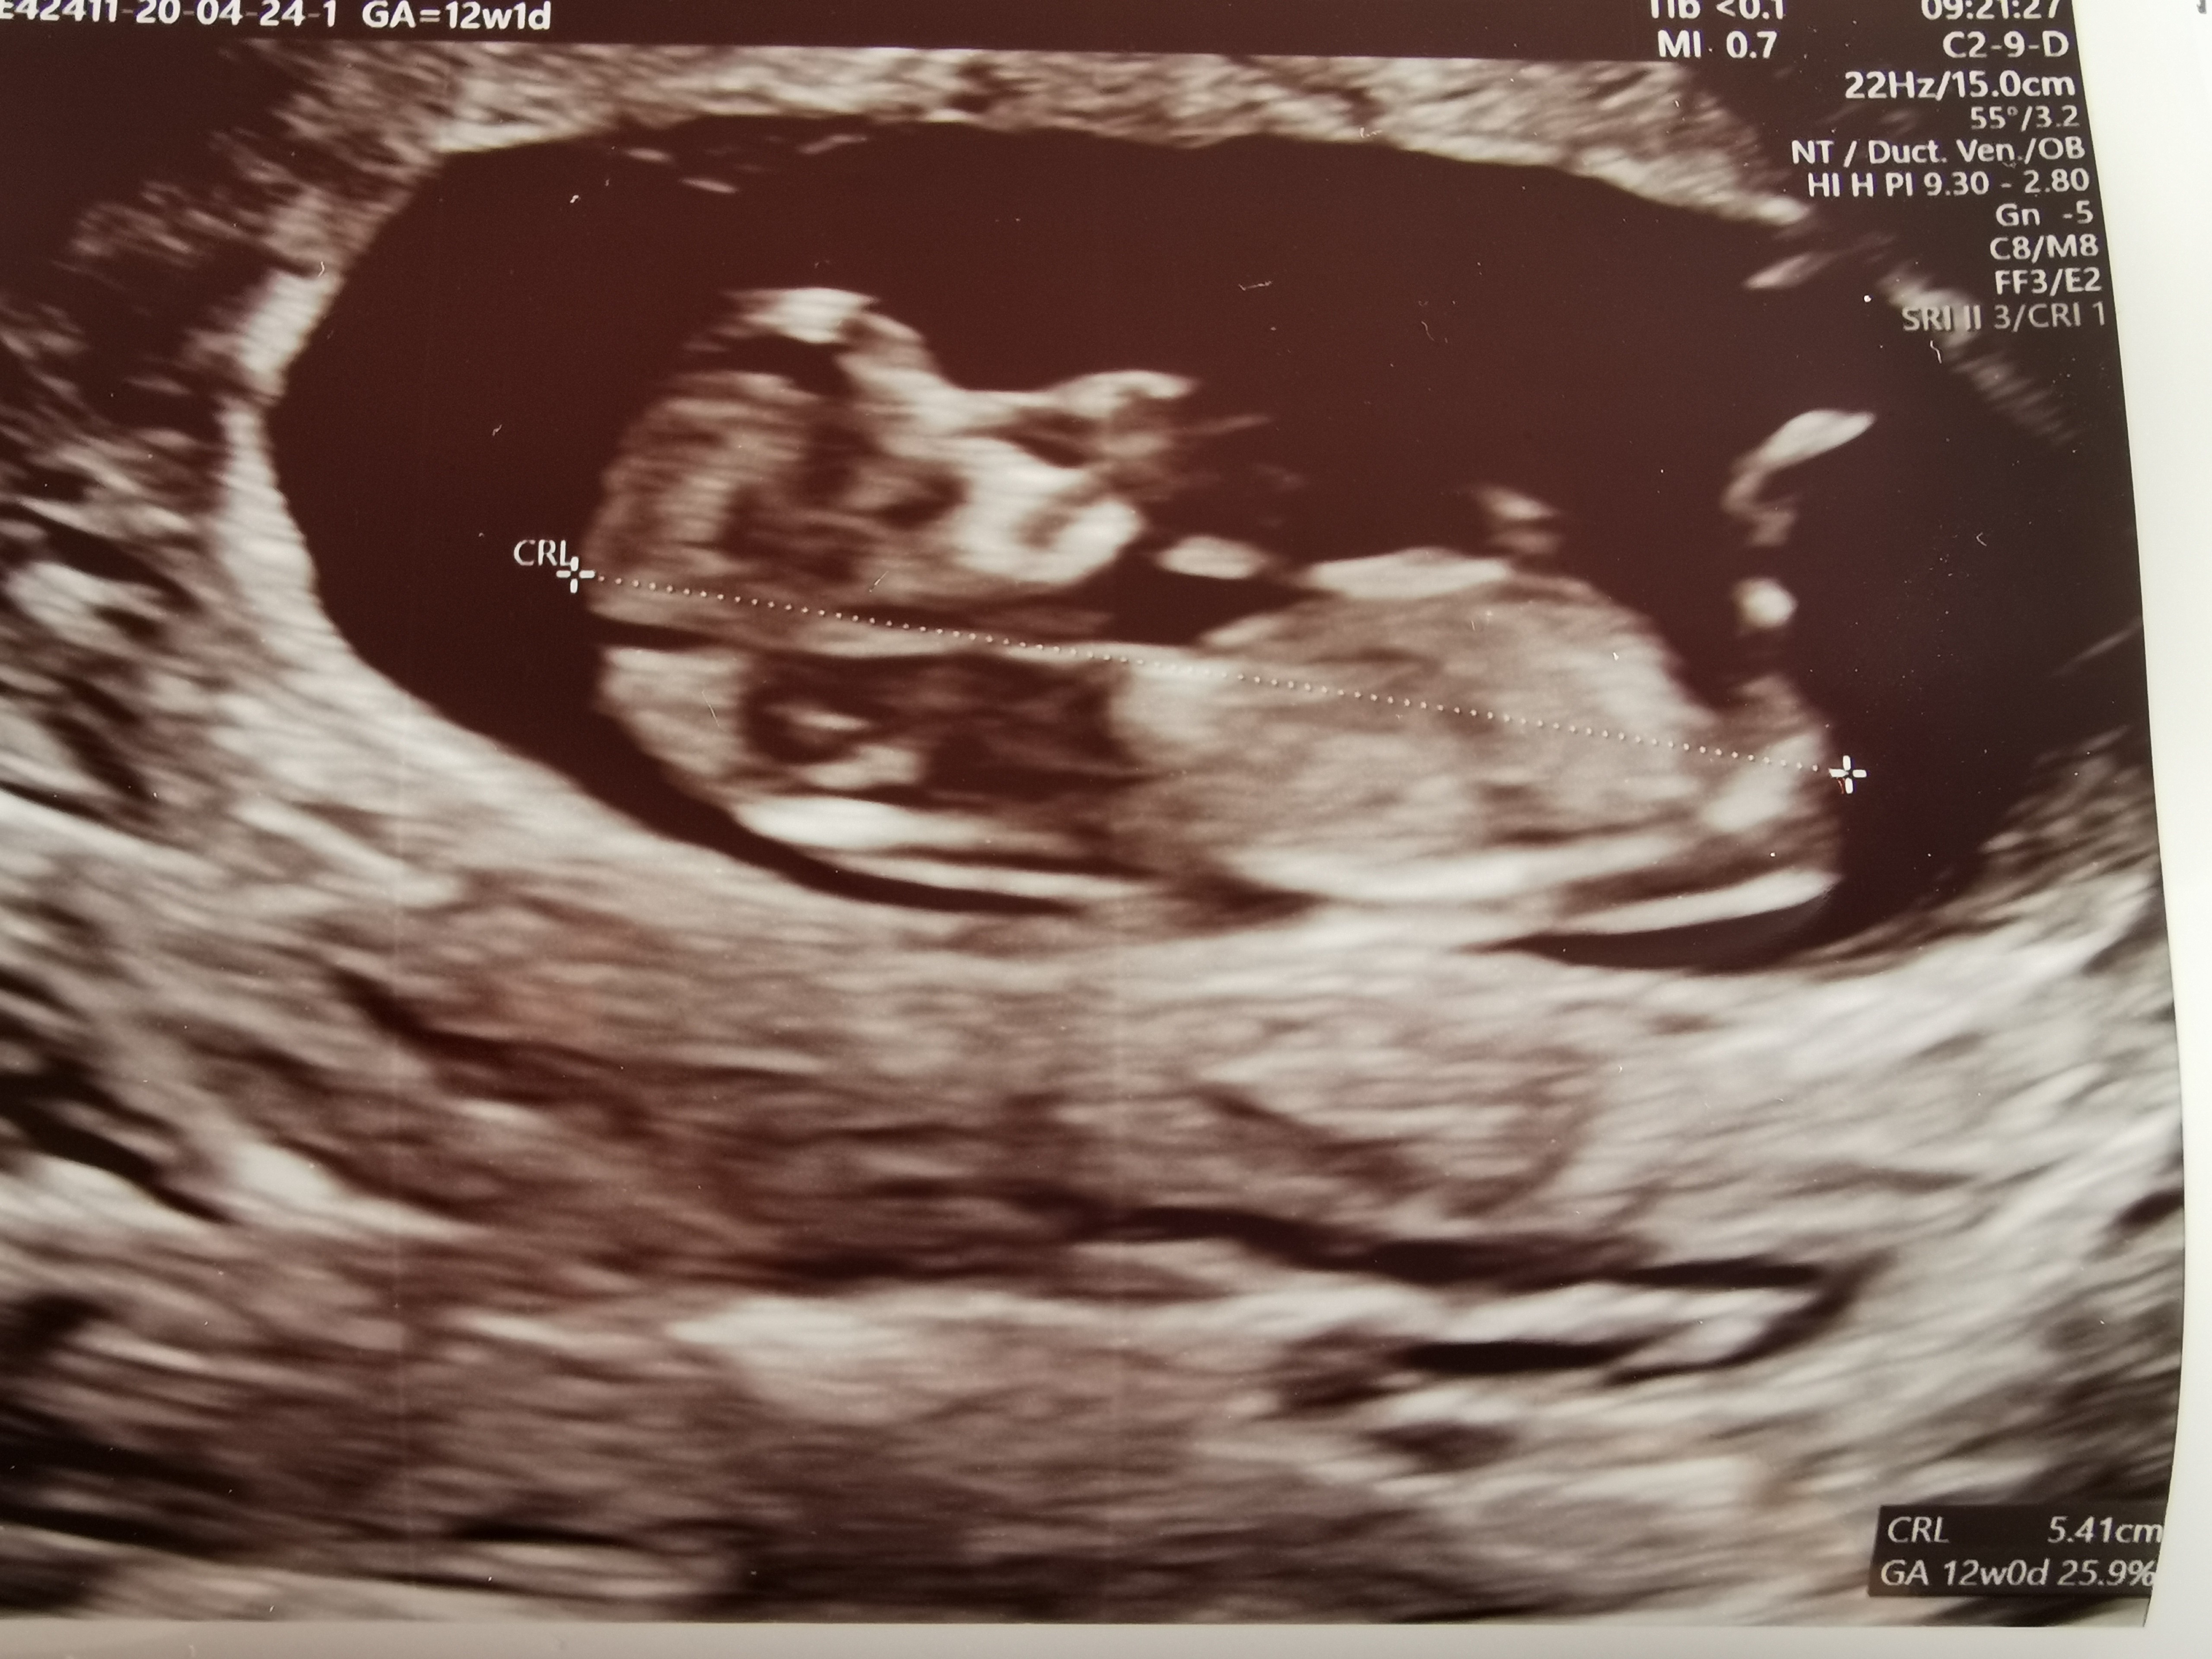

Hej laski 🌷 dziękuję za wczorajsze słowa otuchy przed usg genetycznym. Ja już jestem po, nadenerwowalam się i naczekalam bo opóźnienie jakieś 40 minut... Lekarz akurat był na operacji..

Więc chciałabym wam przedstawić moje dziecię 54, 9mm 🥰 dzisiaj 12+0 wg CRL oraz wg OM, czyli dziecię nadrobilo trochę bo było 5 dni opóźnienia. Termin porodu 06.11, dane z USG: FHR 169/min, NT: 1,1mm, przepływ zylny ok. Kość nosowa uwidoczniona. Po USG ryzyko skorygowane: 21 1:2774, 18 1:3926, 13 <1:20000.

Ciesze się bardzo że jest wszystko ok, dla męża i najbliższych dostałam dostęp przez internet z fotorelacja z USG (kilkanaście zdjęć z usg w dobrej jakości)

Dzieciątko się ruszało, a nawet skakało, pan doktor powiedział że będzie skoczek lub skoczkinii bo płeć narazie jest jeszcze tajemnica :)